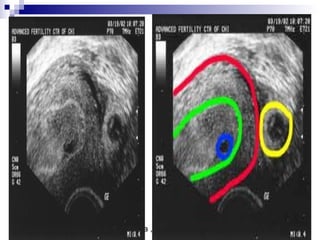

True gestational sacTrue gestational sac must bemust be differentiated fromdifferentiated from

pseudo sacpseudo sac

 Embryonic Vesicle (Primary yolk sac

 Round or oval.

 Double ring )Ring of decidualized

endometrium.

 Fundal or mid-portion of the uterus.

 May occasionally implant low down in the

uterine cavity.

 The "Double Decidual

Sign"consists of two

echogenic rings

surrounding the

hypoechoic gestational

sac.

 The inner ring represents

the chorion, embryonic

disc and decidua

capsularis (*). The outer

ring represents the

decidua parietalis (**).

Uterus outlined red, uterine lining green

Tubal ectopic pregnancy yellow

Fluid in uterus at blue circle is a "pseudosac"

Looks like early pregnancy sac, but is not